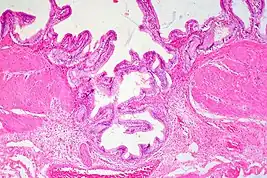

Gallbladder adenomyomatosis is a benign disease of the gallbladder characterized by hyperplasia of the mucosal epithelium and smooth muscle cells inside the muscularis propria.[4][5][6] The excessive proliferation of epithelial cells causes the mucosa to invaginate into the muscular layer lining the gallbladder wall, resulting in characteristic diverticula known as Rokitansky-Aschoff sinuses. These sinuses may be filled with biliary sludge, cholesterol crystals, or gallstones.[4][5][6]

There are three morphologic variants described in the literature – diffuse, segmental, and localized.[5][6] Diffuse, also known as generalized, adenomyomatosis has a widespread distribution of hyperplastic changes and thickening across the gallbladder wall.[5][6] The localized form of adenomyomatosis is also known as a gallbladder adenomyoma (in a similar manner that uterine adenomyoma is the localized variant of adenomyosis). The localized form is a single mass, typically in the fundus, that protrudes into the lumen of the gallbladder in the form of a polyp.[5][6] The segmental form is characterized by its annular (ring-shaped) distribution of adenomyomatosis in the body of the gallbladder, often giving it an hourglass-like appearance.[5][6]

Ultrasound is the preferred initial diagnostic choice for suspected gallbladder disease. Several distinct features of adenomyomatosis are discernable using ultrasound, making it a reliable modality for diagnosis.[4][5][6] The most characteristic features seen on ultrasound are the Rokitansky-Aschoff sinuses, which present either as echogenic foci when filled with biliary sludge/gallstones or anechogenic foci when filled with normal bile.[4][5][6] Other key features that may be seen include wall thickening and ring-down artifacts known as "comet tails" (produced by reverberations of sound between the sinuses).[4][5][6] Ultrasound can also distinguish between diffuse, segmental, and localized variants of adenomyomatosis based on morphology.[5][6]